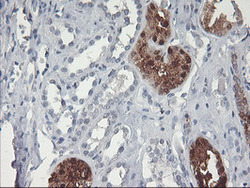

Supportive validation

- Submitted by

- OriGene (provider)

- Main image

- Experimental details

- Immunohistochemical staining of paraffin-embedded Human Kidney tissue within the normal limits using anti-GBA3 mouse monoclonal antibody. (Heat-induced epitope retrieval by 10mM citric buffer, pH6.0, 100C for 10min, TA502533)

- Validation comment

- IHC